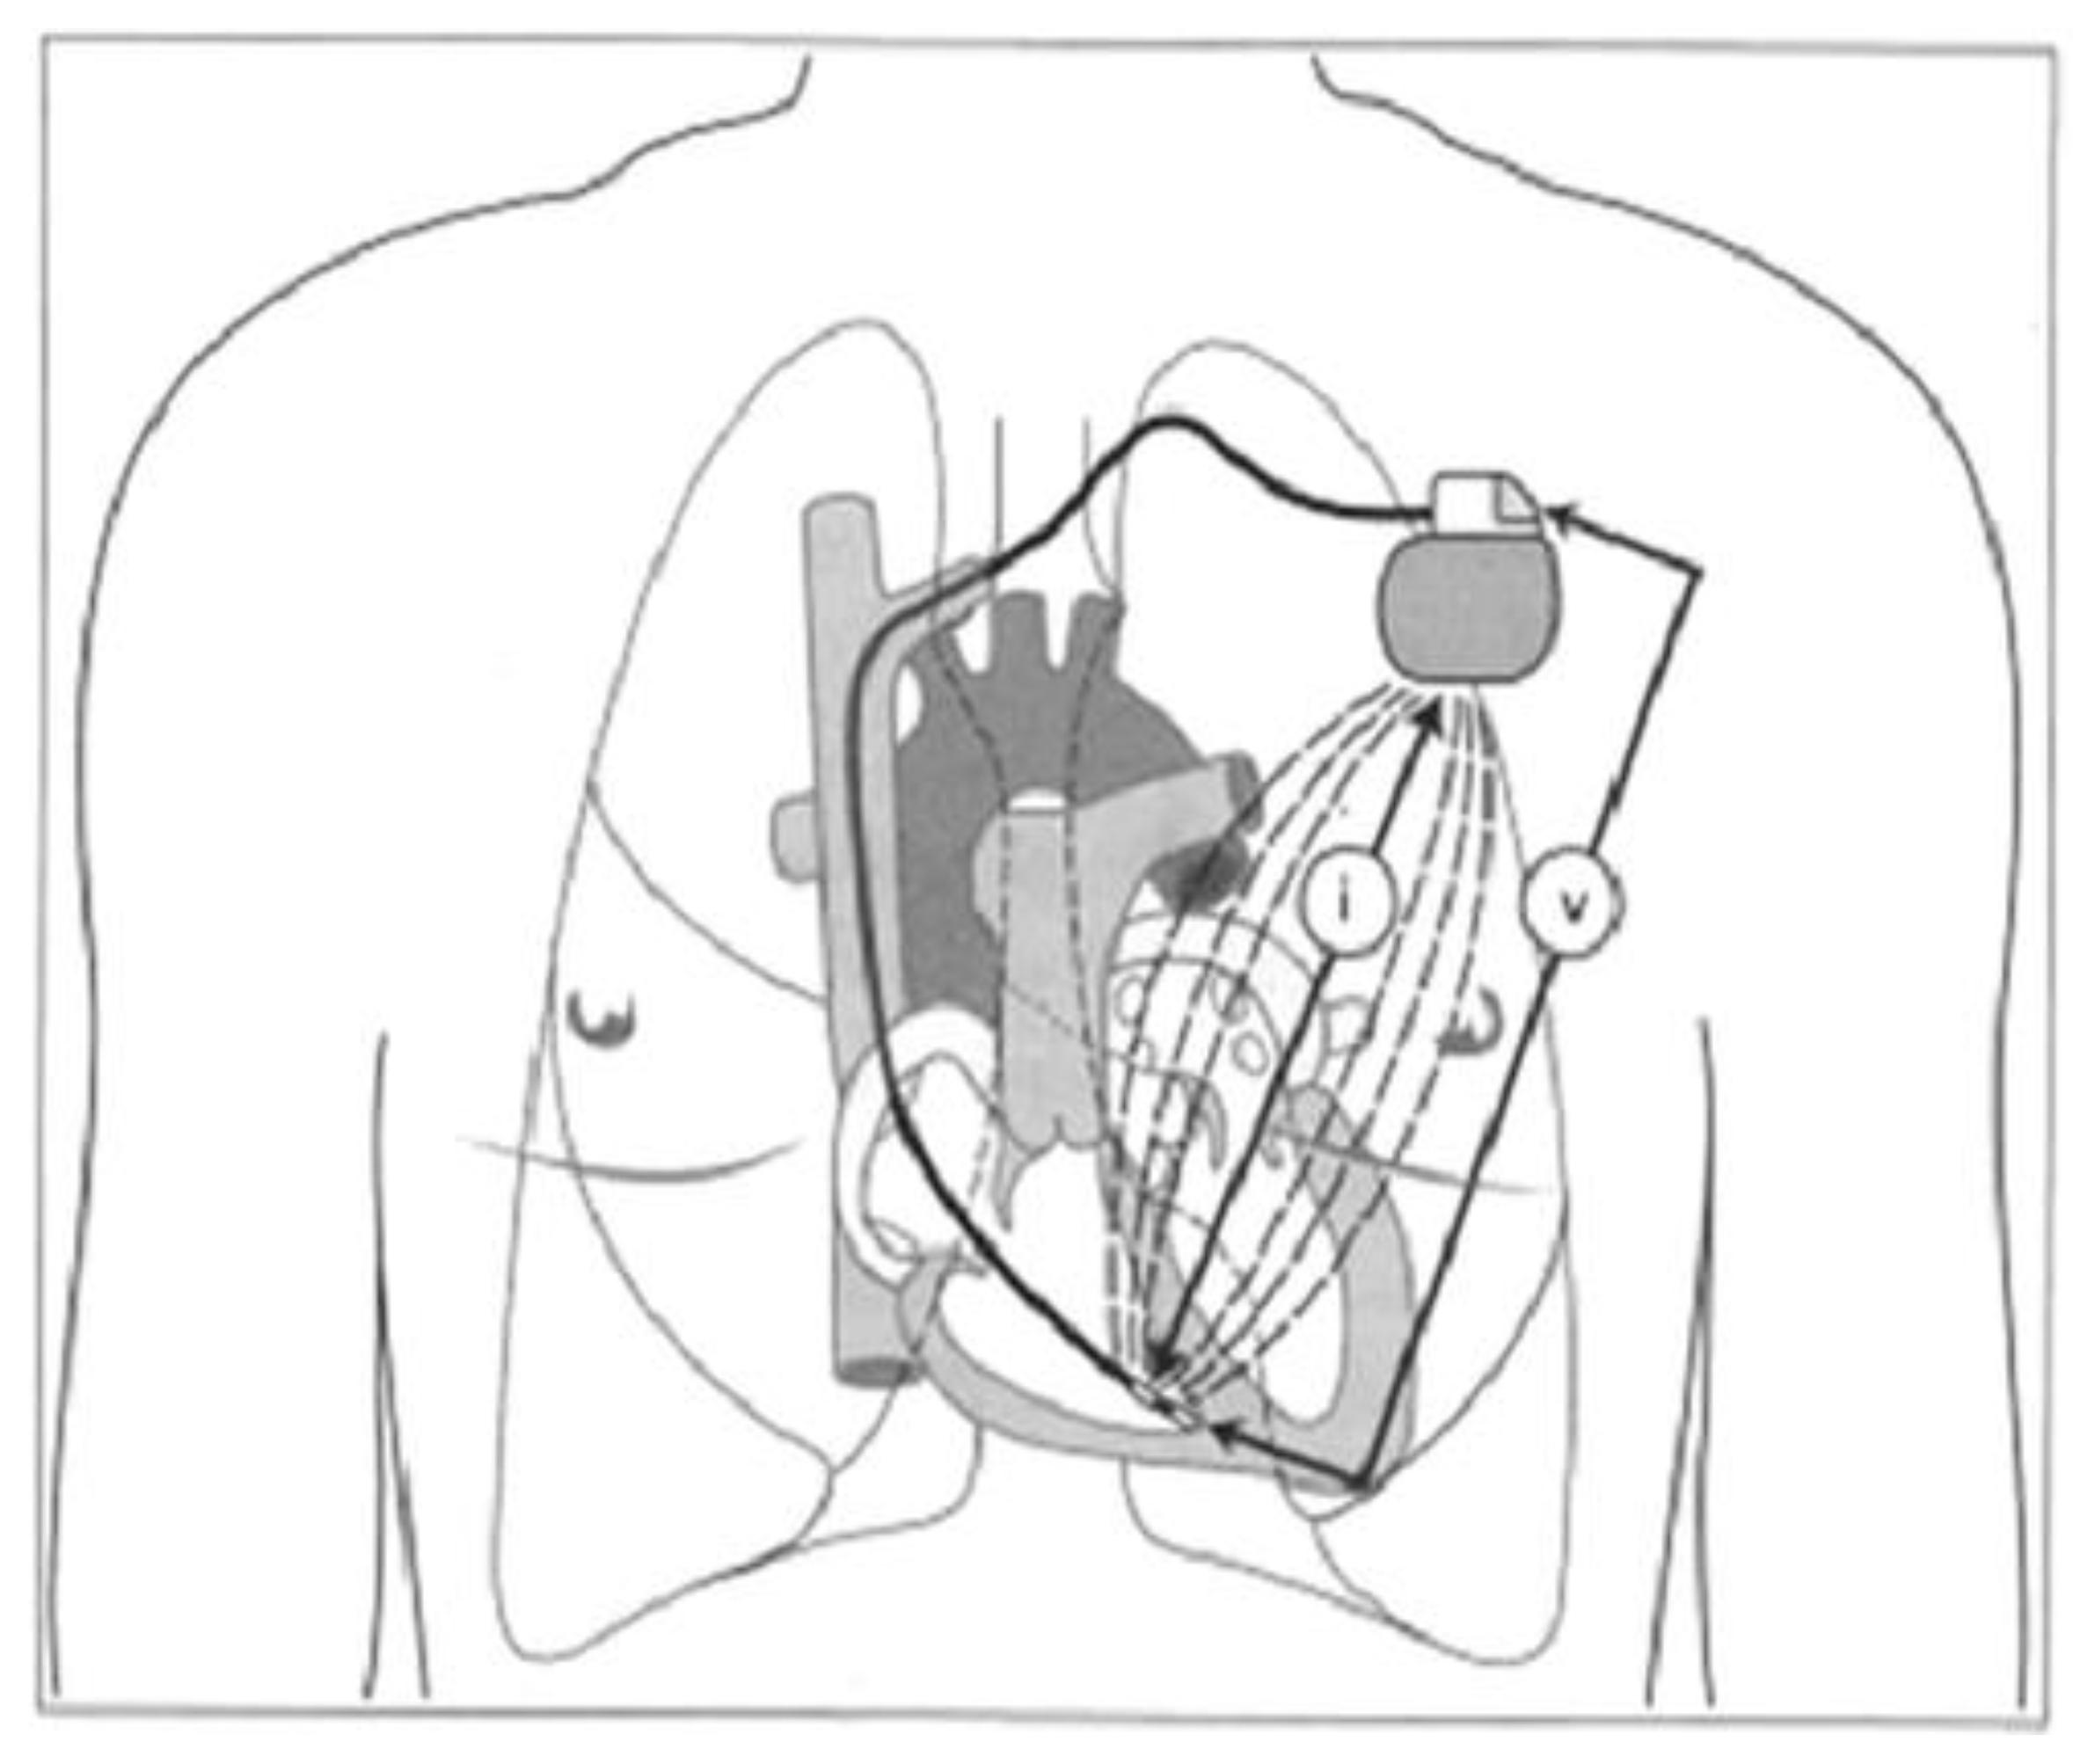

- Chinitz, L.; Ritter, P.; Khelae, S.K.; Iacopino, S.; Garweg, C.; Grazia-Bongiorni, M.; Neuzil, P.; Johansen, J.B.; Mont, L.; Gonzalez, E.; et al. Accelerometer-based atrioventricular synchronous pacing with a ventricular leadless pacemaker: Results from the Micra atrioventricular feasibility studies. Heart Rhythm. 2018, 15, 1363–1371. [Google Scholar] [CrossRef] [PubMed]

- El-Chami, M.F.; Bhatia, N.K.; Merchant, F.M. Atrio-ventricular synchronous pacing with a single chamber leadless pacemaker: Programming and trouble shooting for common clinical scenarios. J. Cardiovasc. Electrophysiol. 2021, 32, 533–539. [Google Scholar] [CrossRef]